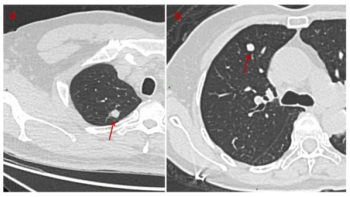

An AI model that includes extracted radiomic features from CT scans more than doubled the sensitivity rate for preoperative prediction of lung cancer recurrence in comparison to traditional TNM staging, according to study findings to be presented at the 2024 American Society of Clinical Oncology (ASCO) Annual Meeting in Chicago.

In comparison to pure solid nodules in patients with non-small cell lung cancer (NSCLC), nodules with a minor ground glass opacity component were associated with over a 38 percent higher rate of recurrence-free survival.

One deep learning model had a 72.4 percent accuracy rate for differentiating between benign and malignant solid pulmonary nodules on non-contrast CT while another deep learning model demonstrated an 87.1 percent AUC for differentiating benign and inflammatory findings.